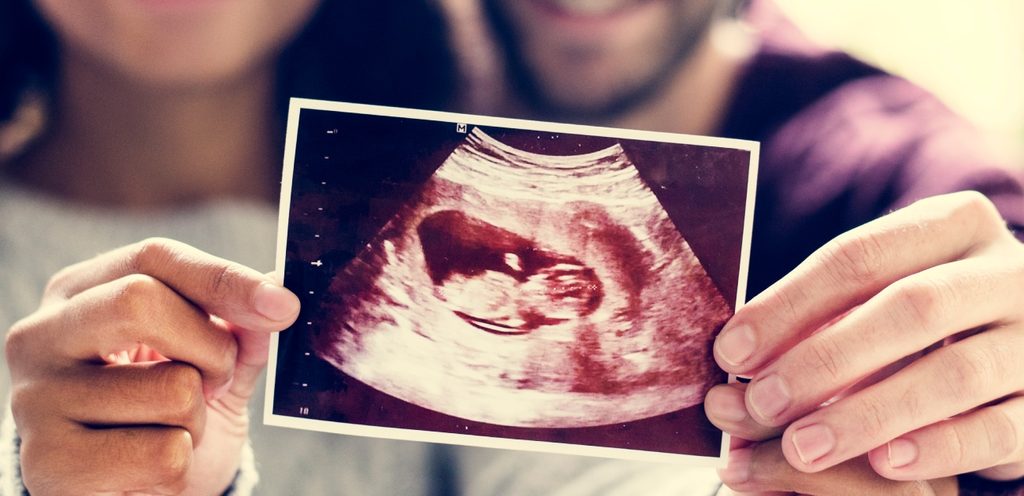

- المرحلة الرابعة: بعد ستة أسابيع تقريبًا من الدورة الشهرية الأخيرة للمرأة الحامل، يمكننا أن نرى قطبًا صغيرًا للجنين، وهي واحدة من المراحل الأولى من نمو الجنين، والذي يتطور جنبًا إلى جنب مع كيس الصفار. إليكِ أيضًا تطوّر الحمل شهر بشهر باختصار